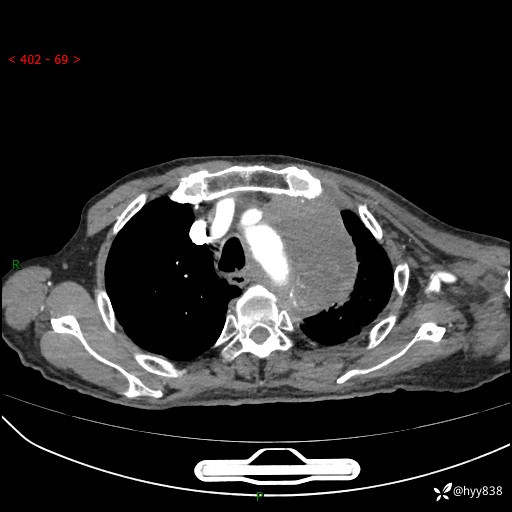

老年男性,气促5月,胸背痛2月。发现肺尖较大肿块,摧枯拉朽之势---结果公布~

现病史:患者于5月前饮酒后突发静息状态下气促不适,无胸闷、胸痛、发热、咳嗽、咳痰等不适,于当地第五人民医院及我院就诊,输液治疗后(具体不详)后气促稍缓解,遂出院后自行口服中草药治疗。近2月出现胸背痛,伴左上肢疼痛、乏力、感觉异常,稍有咳嗽、咳痰,咳黄痰、痰液粘稠,无咳血。为进一步诊治来我院。

胸部CT增强扫描(外院平扫)